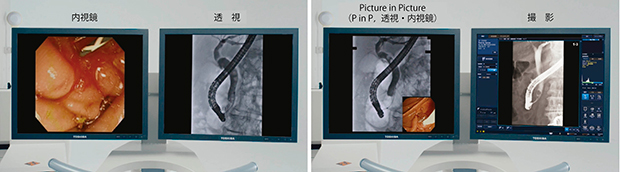

■内視鏡手技のためのモニタレイアウト

必要な情報をわかりやすく表示するモニタレイアウトも重要である(図4)。術中には,透視像と内視鏡の画像を同時に確認する必要がある。さらに,撮影像あるいはMRIやCTなどの関連画像も確認することで,術者は安心して確実な手技を進めることができる1)。例えば,MRCP像を表示し,Cアームを活用してMRCP像と透視像を同じアングルにすることにより,ガイドワイヤの誘導をサポートする。

図4 モニタレイアウトの例(モニタ2面の場合)